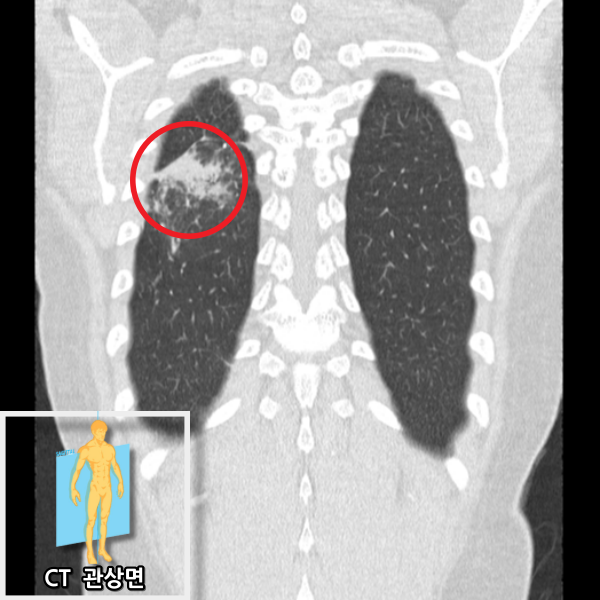

저선량 흉부 CT에서 우하엽에 염증성 고음영이 관찰되며 폐렴에 합당한 소견입니다. 이전 결핵을 앓은 적이 있어 추가 치료가 필요하다고 판단하여 상급병원으로 전원하였습니다.

• CT 관상면 CT 관상면